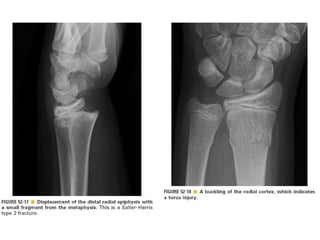

Skeletal trauma was presented by Dr Laith Fadhel with reference to Grainger's Diagnostic Radiology textbook. The presentation covered skeletal trauma as assessed through diagnostic radiology techniques. Key findings and treatments for skeletal injuries were likely discussed.